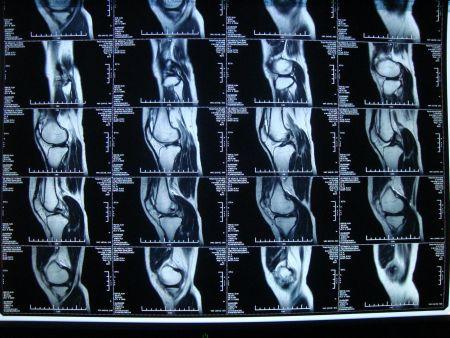

核磁共振是当代生活无法规避的一个课题。经由核磁共振仪这项科学化仪器,人类的身体内部结构迅速神奇的透明化,内部器官的成像高效透露身体的早期病变,医者对症下药,及时维护病人们的生命健康。

随着MRI技术的日趋成熟,医学的科学性也随之提升,从深处溯源,核磁共振技术就是利用水体中氢原子的信号反应来确定水分子在生物体内的分布结构,从而探测人体生理结构的完整性。

人类身体的三分之二由水构成,水又由氢原子和氧原子构成。当我们的肉身暴露在磁核共振仪下,就会引起氢原子的共振反应,通过这样的聚合磁场,人体内部的水分子就会呈现出一定的梯度,从而形成人体内部结构的影像。